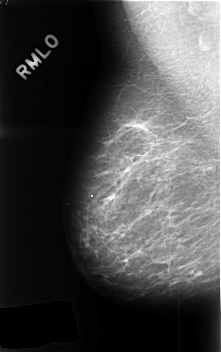

Digital Database for Screening Mammography

Volume: benign_without_callback_02 Case: C-0444-1

C_0444_1.RIGHT_MLO

filename C-0444-1

DATE_OF_STUDY 30 6 1995

PATIENT_AGE 51

FILM_TYPE REGULAR

DENSITY 1

DIGITIZER LUMISYS LASER

RIGHT_CC LINES 4584 PIXELS_PER_LINE 2912 BITS_PER_PIXEL 12 RESOLUTION 50 NON_OVERLAY

RIGHT_MLO LINES 4576 PIXELS_PER_LINE 2872 BITS_PER_PIXEL 12 RESOLUTION 50 NON_OVERLAY